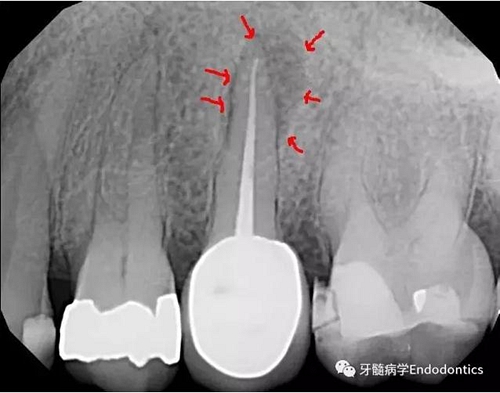

圖3.術(shù)后X線(xiàn)片示根充物距離根尖有3mm的距離